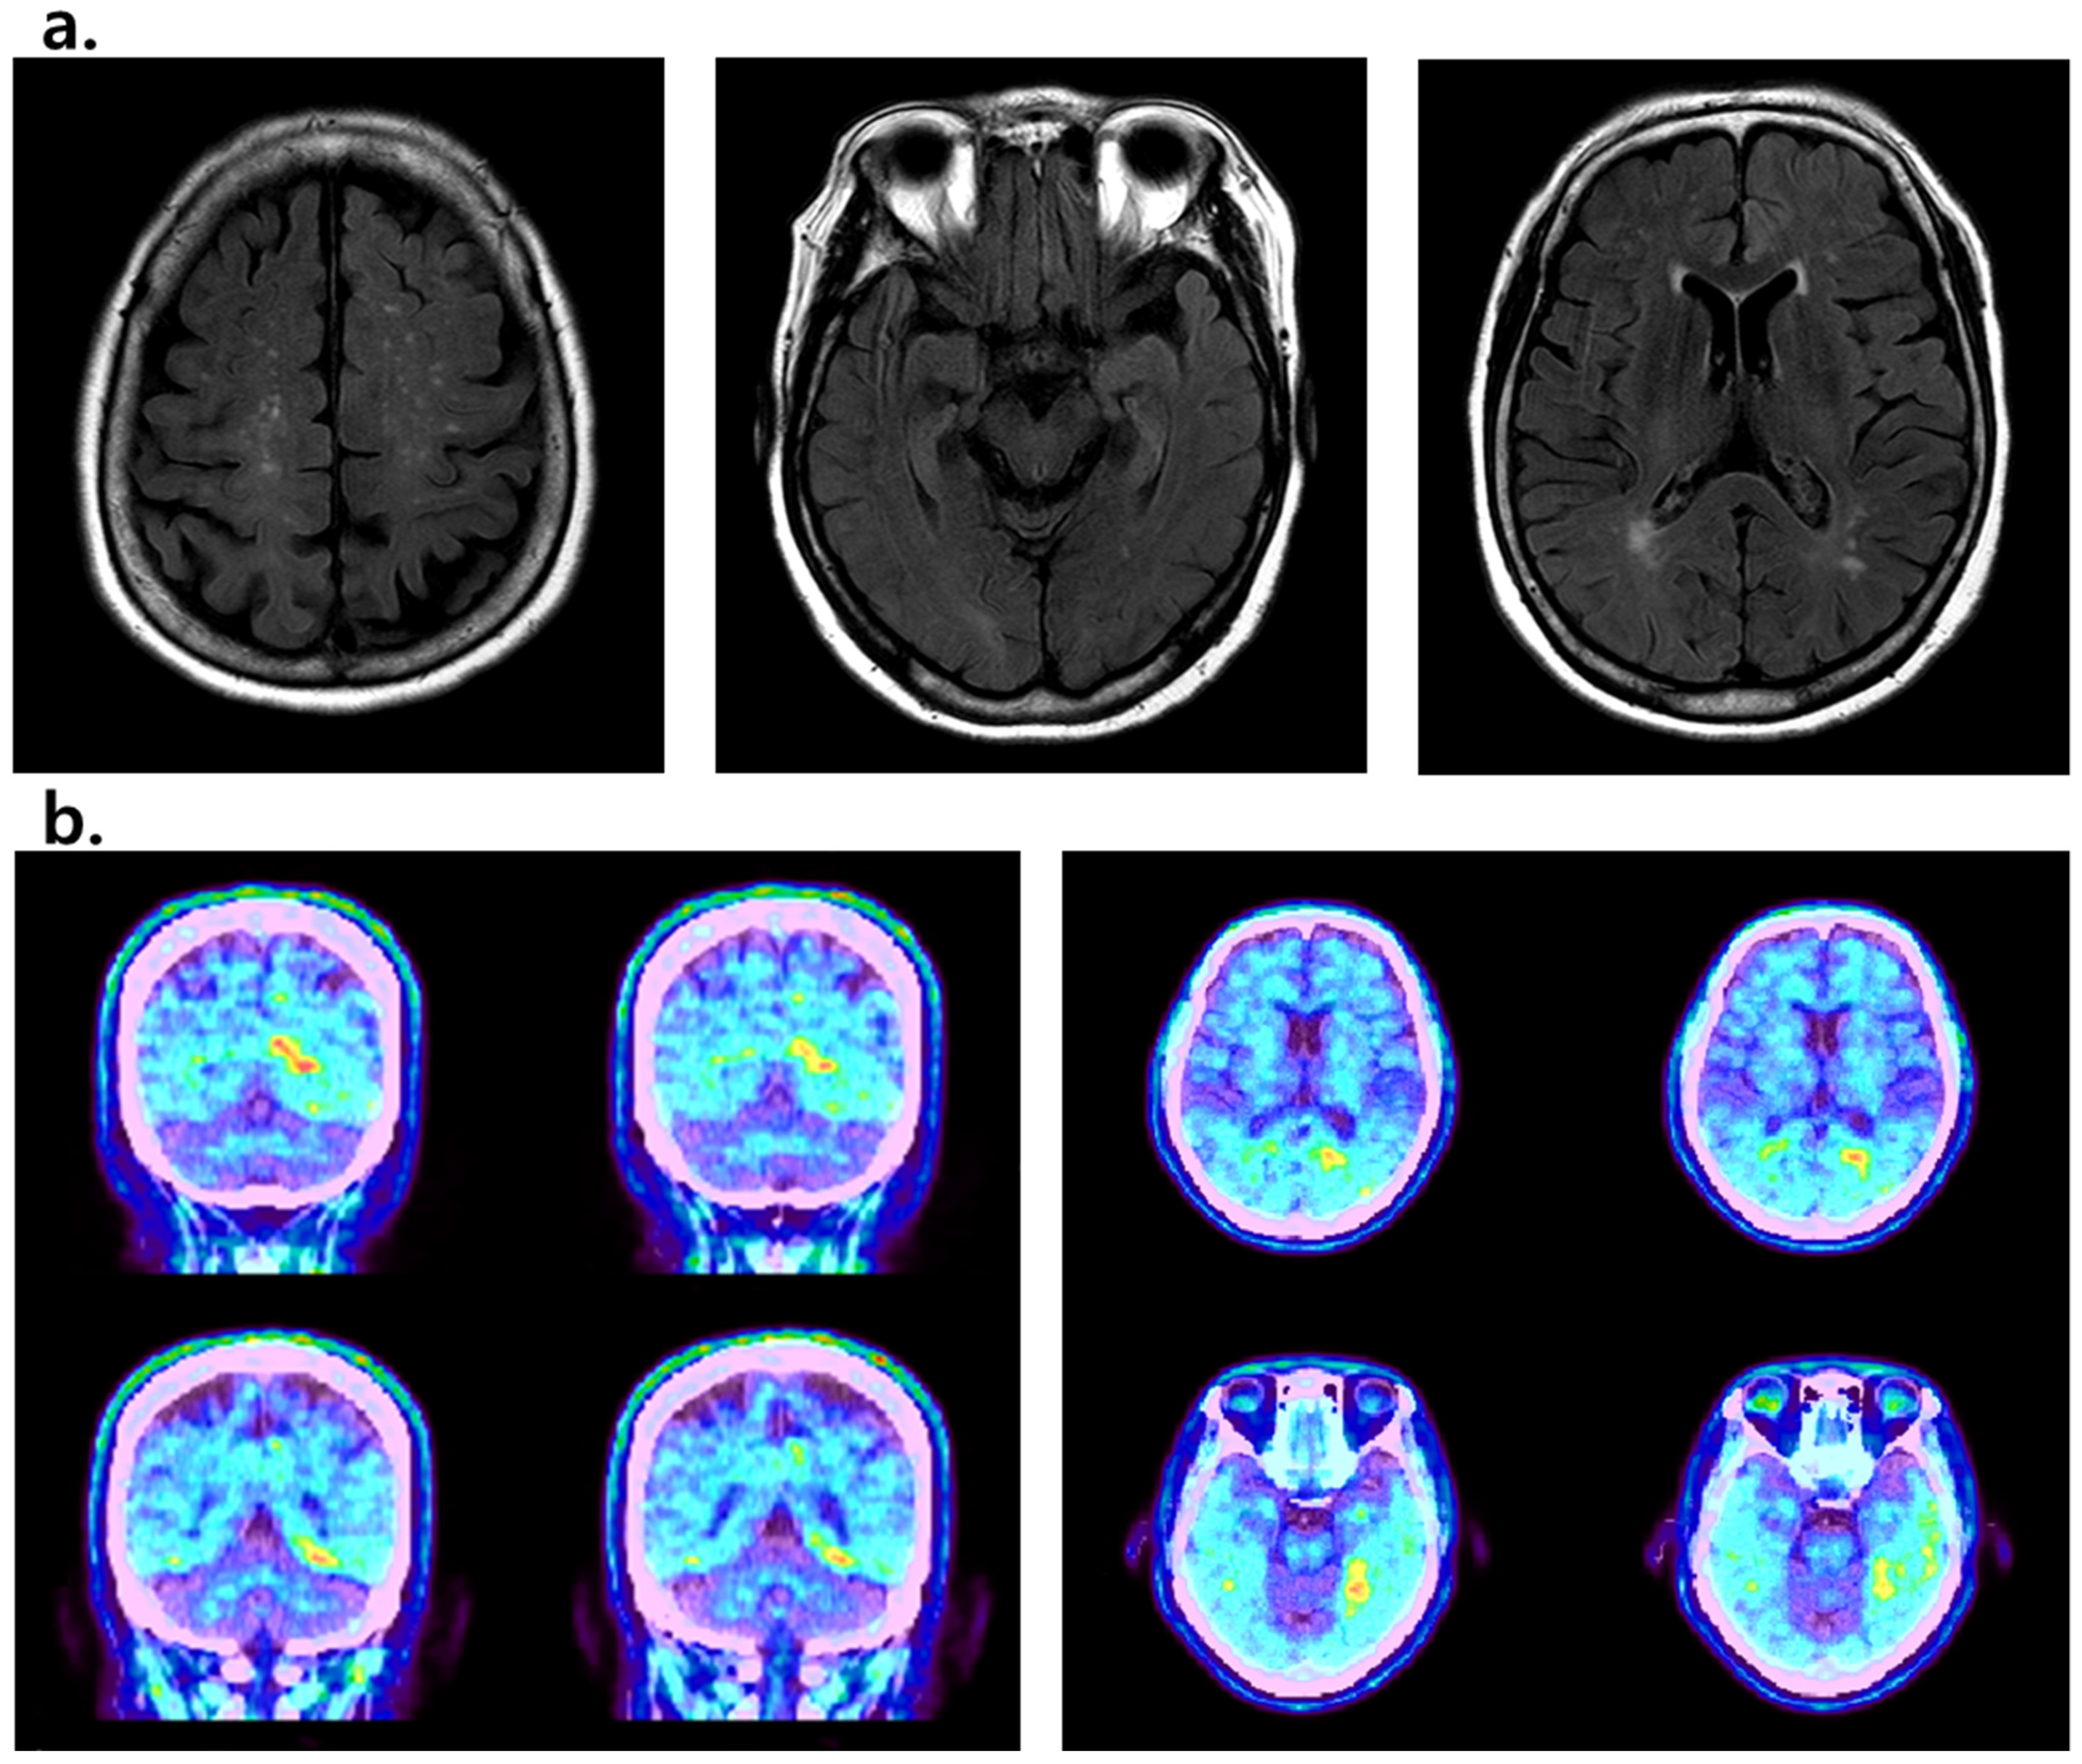

2. Case Presentation

4. Results